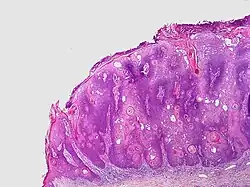

Micrograph of a seborrheic keratosis (H&E stain, scanning magnification)

Visual diagnosis is made by the "stuck on" appearance, horny pearls or cysts embedded in the structure. Darkly pigmented lesions can be challenging to distinguish from nodular melanomas.[10] Furthermore, thin seborrheic keratoses on facial skin can be very difficult to differentiate from lentigo maligna even with dermatoscopy. Clinically, epidermal nevi are similar to seborrheic keratoses in appearance. Epidermal nevi are usually present at or near birth. Condylomas and warts can clinically resemble seborrheic keratoses, and dermatoscopy can be helpful to differentiate them. On the penis and genital skin, condylomas and seborrheic keratoses can be difficult to differentiate, even on biopsy.

A study examining over 4,000 biopsied skin lesions identified clinically as seborrheic keratoses showed 3.1% were malignancies. Two-thirds of those were squamous cell carcinoma.[11] To date, the gold standard in the diagnosis of seborrheic keratosis is represented by the histolopathologic analysis of a skin biopsy.[12]